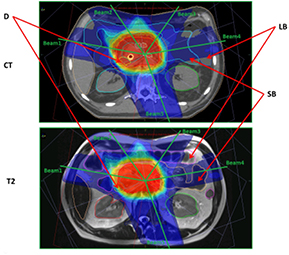

The effects on uniform rED assignment on T2-based plans (T2_D1_B1_O0 and T2_D1_B1_O1) were found to be larger (figures 4(a) and (b)) than the Gold St. When optimization of the pancreas and prostate plans was performed, target coverage was achieved without violating OAR planning constraints; however this does result in larger/smaller difference in OAR doses compared with the Gold St (figures 4(c) and (d)). These large differences in IMRT plan quality metrics was partly due to changes in anatomical shape, volume and position of the organs/tissues in between image acquisitions (figures 5 and 6). However, the DVPs for the OAR still meet the planning criteria in table 1 for both pancreas and prostate IMRT plans (i.e. T2_D1_B1_O1 in tables 10(a) and (b)). The central axis (CAX) of the beams on the T2 images pass through different tissues (i.e. beams3 and 4 in figure 5 pass through different amounts of small bowel, large bowel and NST) with slightly different rED, shape and volume that lead to small changes in absolute dose, which yield very large percent changes compared to the Gold St. For example, panc2's stomach Dmax on the Gold St was 17 Gy and 52.2 Gy on T2_D1_B1_O0 (a +183.4% difference but still clinically acceptable). Optimization of the panc2 plan reduced the stomach Dmax to 51.9 Gy, which is within clinically acceptable limits but still a +178.8% difference. A similar observation was made on prost1, where the bladder Dmean on the Gold ST were 9.2 Gy but increased to 12.7 Gy (+37.7% difference) on T2_D1_B1_O1. Re-optimization on the T2 reduced the bladder mean dose to 9.62 Gy, which is clinically acceptable but still 4.1% higher than the Gold St. Additional examples of large increases in DVP that remain within clinical acceptable range in table 1 include the 6% increase in rectum V45, which is a difference of 22.5% and 28.6% between Gold St and T2_D1_B1_O1, respectively.

Standard image High-resolution imageFigure 5. Pancreas CT and T2 images. Abbreviations: CT—axial slice through isocenter on pancreas IMRT CT data set; T2—axial view through isocenter on prostate IMRT T2 data set; D—duodenum; LB—large bowel; SB—small bowel; Beam1—beam with central axis at a gantry angle of 280°; Beam2—beam with central axis at a gantry angle of 325°; Beam3—beam with central axis at a gantry angle of 35°; Beam4—beam with central axis at a gantry angle of 80°; and Beam5—beam with central axis at a gantry angle of 160°.

Download figure:

Standard image High-resolution imageFigure 6. Prostate CT and T2 images. Abbreviations: CT—sagittal view through isocenter on prostate IMRT CT data set; T2—sagittal view through isocenter on prostate IMRT T2 data set; B—bladder and R—rectum.